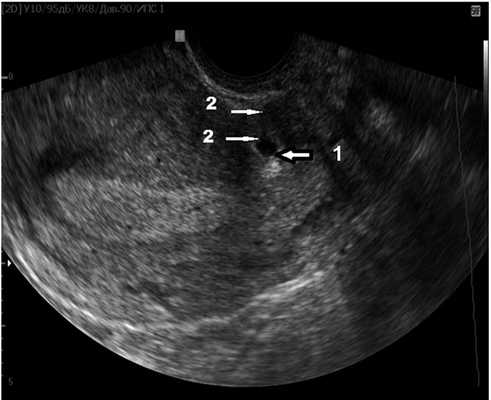

При обращении в поликлиническое отделение ГБУЗ МО МОНИИАГ сроки диагностики эктопической беременности в рубце были следующими: 6—7 нед — у 7 (36,84%) беременных; 9—10 нед — у 10 (52,63%); 13 недель — у 2 (10,53%) пациенток. Прогрессирующая беременность отмечена у 13 (68,4%) женщин, неразвивающаяся беременность — в 6 наблюдениях (31,6%). У 2 (10,5%) пациенток при сроке гестации до 7 нед выявлена типичная локализация плодного яйца в проекции «ниши», истмоцеле, не отмечено признаков несостоятельности рубца на матке, толщина резидуального миометрия составила от 3 до 5 мм (рис. 1).

Рис. 1. Беременность в рубце без признаков его несостоятельности.

Стрелками отмечено: 1 — плодное яйцо; 2 — сохранный миометрий.